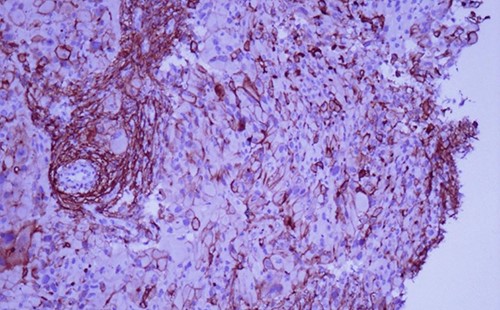

A 42-year-old man with no clinical history presented with a non-ulcerated polypoid skin nodule of the front side of the chest wall, which had grown over a period of 6 months, measuring 1,8 × 1,5 cm (Fig. 1). The lesion was removed completely with tumor-free margins of 0,5 cm. Microscopically, the tumor was composed of a diffuse infiltrate of polygonal cells with abundant granular cytoplasm and vesicular nuclei (Figs 2 and 3). There was no atypia or necrosis. The average mitotic count was one to two per 10 high-power field. Immunohistochemistry showed positive expression for CD10, CD68 and ALK with negative staining for CK AE1/AE3, CD34, S100 and HMB45 (Figs 4 and 5). No recurrence was noted during follow-up of 6 months.

The tumor is composed of epithelioid cells with abundant granular cytoplasm and vesicular nuclei (magnification at ×400).

Microscopically, DNNGCT are well circumscribed and composed of large spindled or polygonal to epithelioid cells with abundant granular cytoplasm [2, 4, 5]. The nuclei are vesicular with a single prominent nucleolus [7]. The mitotic index varies from 1 to 9 per 10 high-power field. A subset of this tumor show atypical cytologic features including nuclear pleomorphism and increased mitoses [1, 2, 4]. These histological features do not seem to correlate with a worse clinical behavior [1, 2, 4].